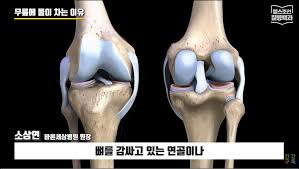

무릎에 물이 차는 증상, 즉 '관절 삼출액'의 발생은 여러 가지 원인에 의해 나타날 수 있습니다. 보통 무릎 관절 내부에 있는 윤활액이 과도하게 생성되거나, 외부적인 요인에 의해 염증이 생겨 발생하는 경우가 많습니다. 여기서 무릎에 물이 차는 현상을 발생시키는 대표적인 원인들을 살펴보겠습니다.

- 슬개골 연골연화증: 슬개골의 연골이 약해져 염증과 부기가 발생합니다.